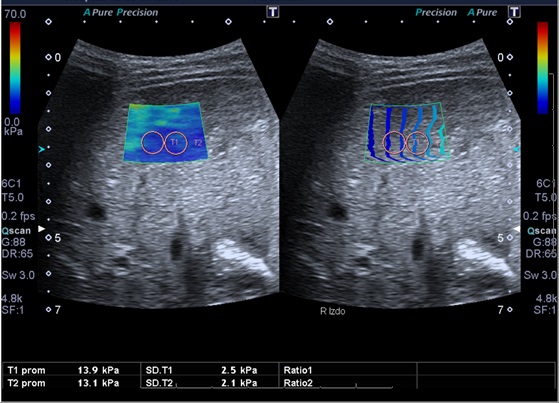

Tras el diagnóstico de síndrome de Joubert, se inició seguimiento multidisciplinar del paciente. Durante el seguimiento posterior, a los 10 años de edad, se detecta en control analítico una hipertransaminasemia creciente con patrón de colestasis sin hiperbilirrubinemia, y con tendencia a la trombopenia. Se deriva a consultas de Gastroenterología del hospital terciario de referencia, para proceder a un despistaje de hipertensión portal. En dicho centro, como primera etapa, se solicitó ecografía abdominal con Doppler y elastografía hepática. Ambas pruebas muestran alteraciones. De especial valor resulta la elastografía, en la que se objetivan unos valores compatibles con aumentado del grado de rigidez (de media, 15,8 kPa) (Figs. 1 y 2). En la ecografía Doppler se constató una hepatomegalia leve, sin alteraciones significativas de los flujos sanguíneos a través de la vena porta, arteria hepática y venas suprahepáticas.

| Figura 2. Valores numéricos de elastografía y velocidad de la transmisión ecográfica. A mayor cifra de kPa, mayor será la rigidez del hígado (y, por tanto, mayor será el grado de fibrosis) |

En estos pacientes es importante evaluar, como primer paso, la realización de elastografía hepática, para estimar la rigidez el hígado y, por consiguiente, si puede existir fibrosis o no.

Los grados de fibrosis se dividen en cinco, siendo F0 equivalente a hígado sano y F4, máxima fibrosis o cirrosis. El resultado de la elastografía se expresa en kilopascales (kPa), y se correlaciona con los grados de fibrosis (F0-F4). El rango de equivalencias varía en función del tipo de elastografía que se realice, por lo que estos valores no son comparables entre técnicas elastográficas distintas, pero si el grado de fibrosis en que se clasifiquen1-6. Se trata de una técnica radiológica sencilla y no invasiva, que nos permitirá realizar una monitorización del hígado, permitiendo repetirla periódicamente al tratarse de una exploración segura para el paciente. No obstante, hay que recalcar que el “patrón oro” diagnóstico de la fibrosis hepática es la biopsia.